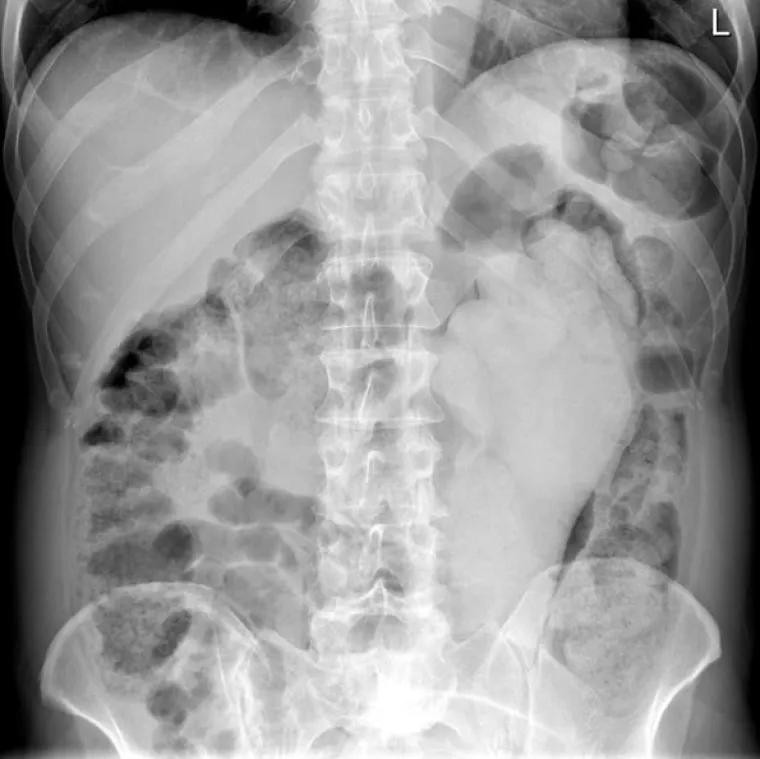

Doktori podijelili povjerljive slike pacijenata koji su u sebe ugurali sve i svašta

Gumena šaka